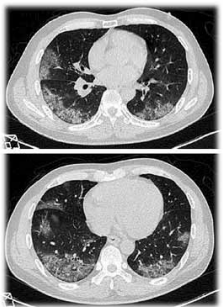

Homem, 39 anos, obeso e dislipidêmico, procurou atendimento médico ambulatorial devido sensação de febre (não medida), tosse seca e odinofagia há seis dias. Recebeu medicação sintomática e aconselhamento para manter-se em repouso relativo domiciliar. Dois dias após o atendimento inicial, necessitou internação hospitalar por piora clínica, tosse mais acentuada e dispneia em repouso. Exame físico: regular estado geral, corado, hidratado, anictérico, acianótico e taquipneico leve; PA = 120 x 80 mmHg; SpO₂ em ar ambiente = 86%; ausculta pulmonar com estertores difusos e com tiragem intercostal leve. Foi realizada tomografia de tórax, conforme ilustração a seguir.